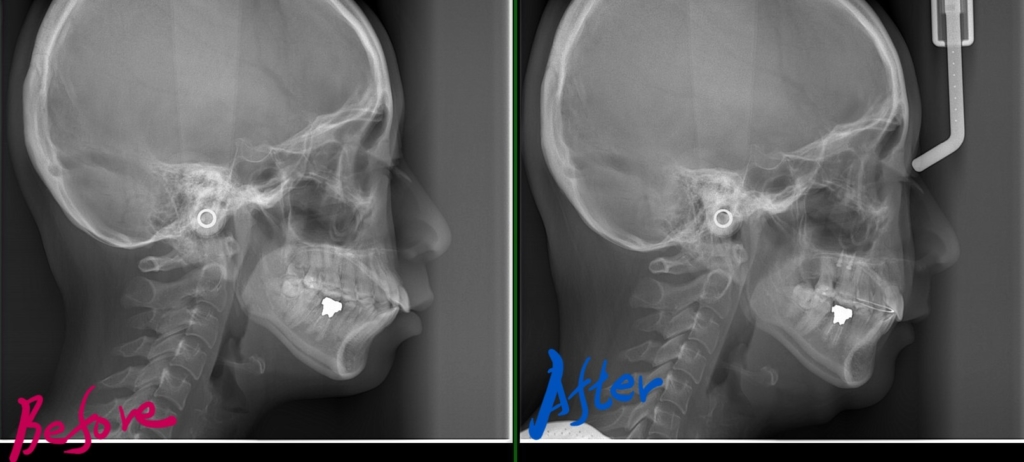

レントゲン写真でも比較してみましょう

左側が矯正治療前、右側が矯正治療後